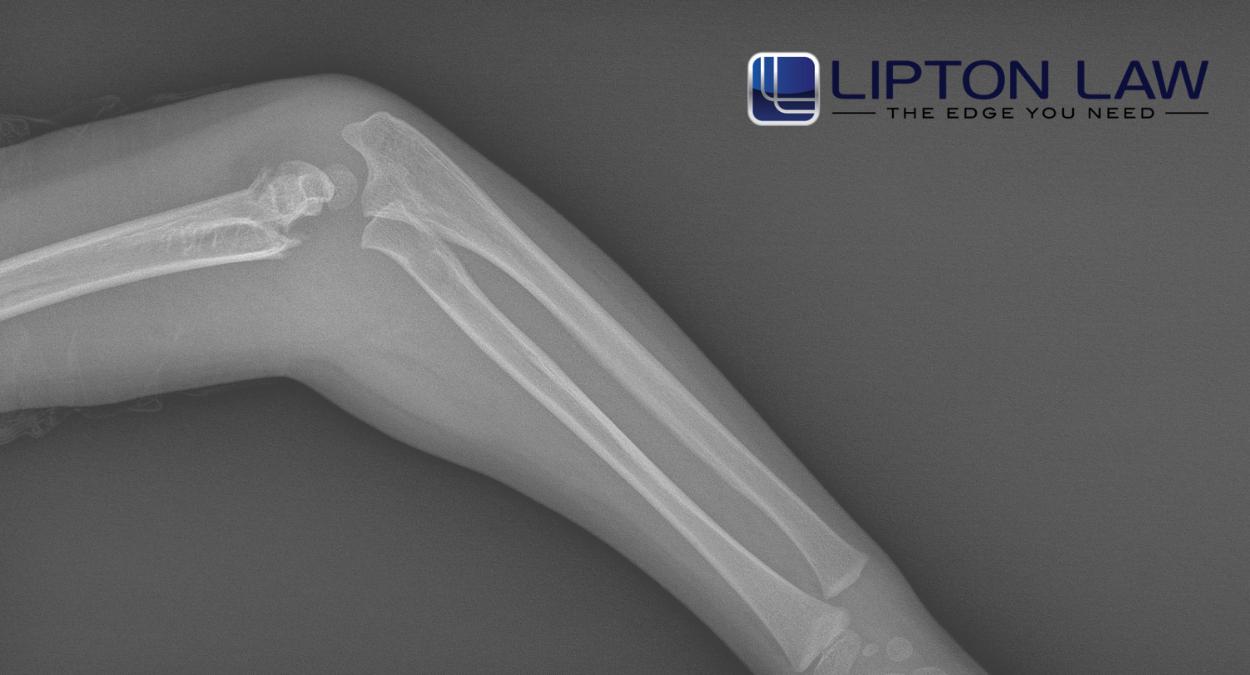

What seems like a simple bone break can lead to serious medical issues that affect your daily life. Medical professionals rely on imaging such as an X-ray, CT scan, or magnetic resonance imaging (MRI) to diagnose bone fractures and assess damage to surrounding tissue and blood vessels. Some fractures cause severe injuries that require surgery, physical therapy, and close medical monitoring. During recovery, physical pain can limit movement and make routine tasks difficult. Certain injuries also lead to complications such as infections, nerve damage, or improper healing.